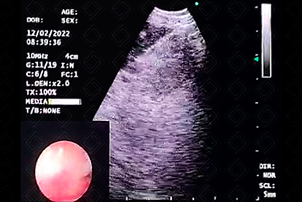

Texto alternativo para a imagem Figura 2

Texto alternativo para a imagem Detalhe do exame de imagem da Figura 2. Ultrassom endobrônquico radial mostrando massa entremeada por parênquima pulmonar. Créditos: Dra. Bruna Provenzano - Rio de Janeiro/RJ